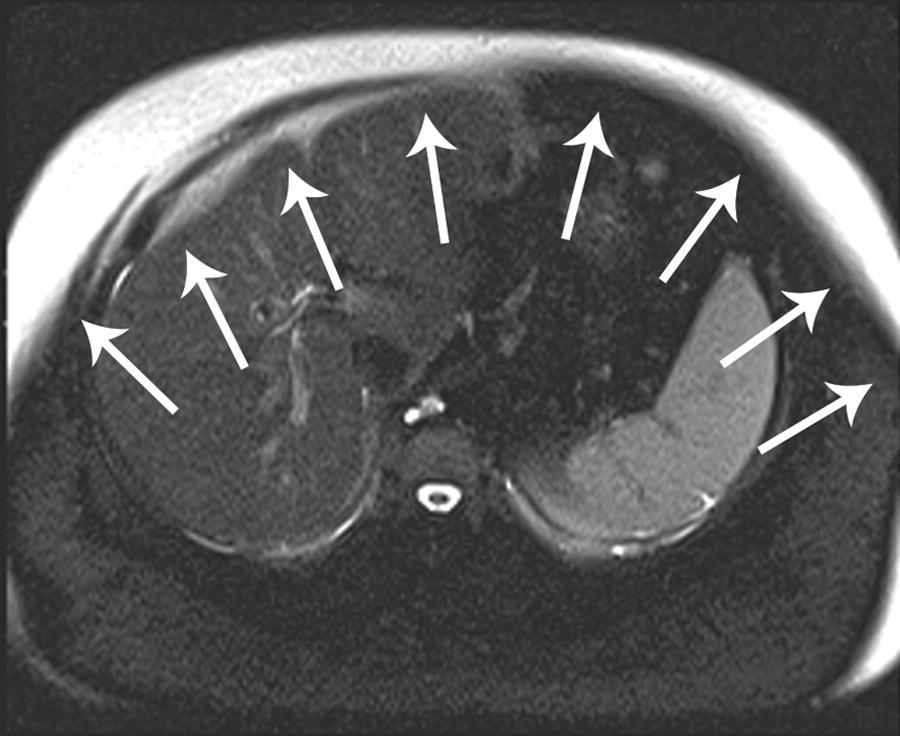

13 A woman with chronic renal failure, fatigue, and decreasing hematocrit.

52 A patient with cirrhosis underwent abdominal evaluation with ultrasound followed by CT. A spectral Doppler ultrasound image and two arterial phase CT images are shown. What is the finding?

A. Hepatopedal flow in the portal vein

B. Respiratory variation in the portal vein

C. Arterioportal shunting

D. Cavernous transformation of the portal vein